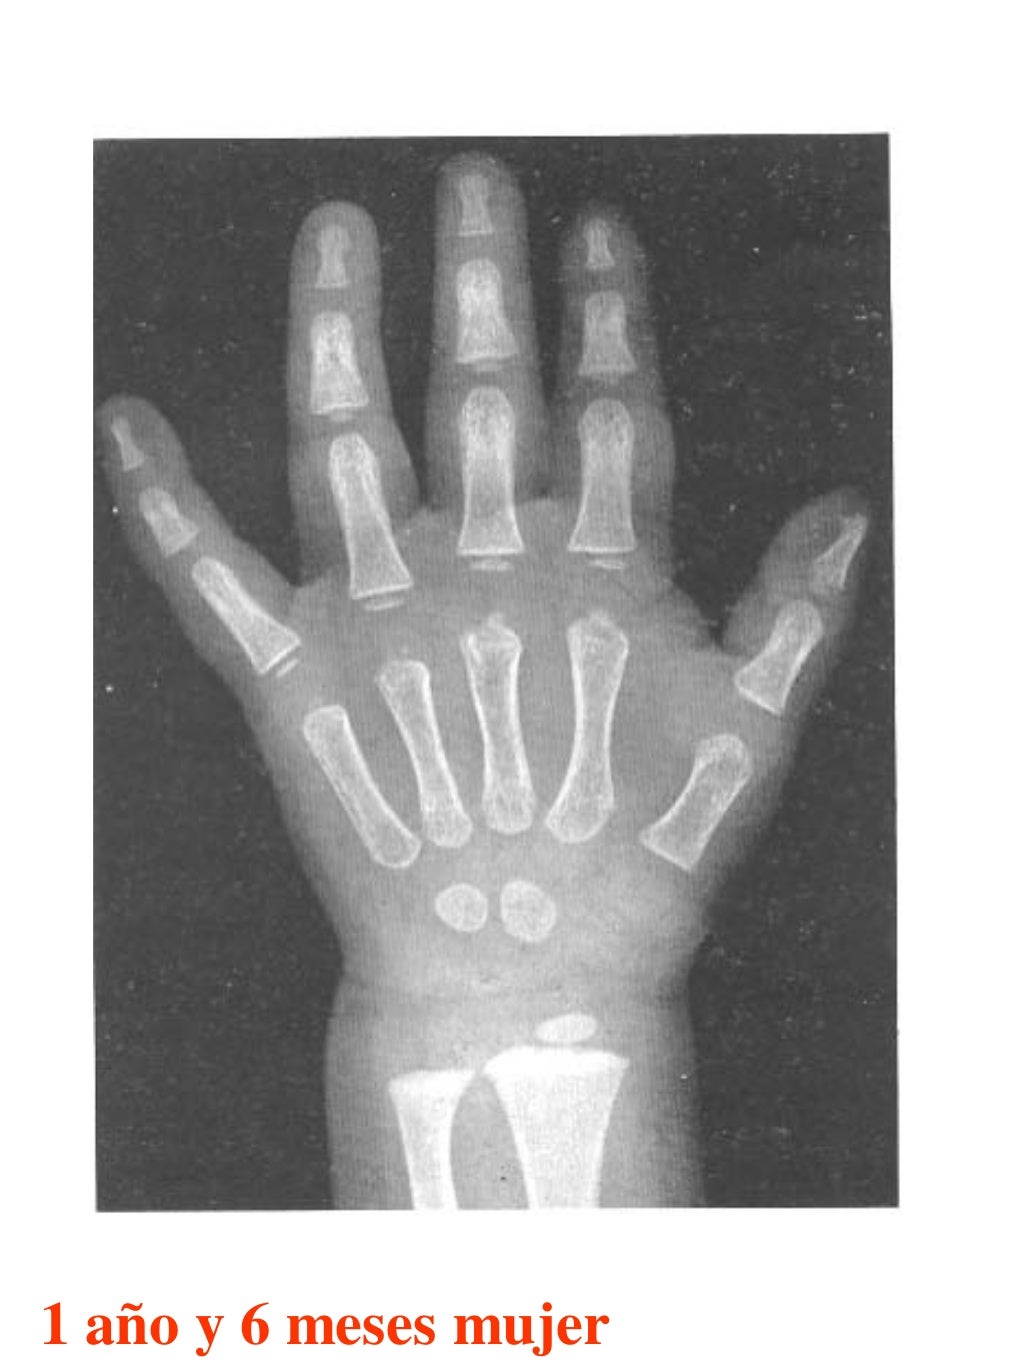

Tablas De Greulich Y Pyle . Scribd is the world's largest social reading and publishing site. This systematic review summarizes the. The radiographic atlas of skeletal development of the hand and wrist by ww greulich and si pyle is a classic radiological. The standards established by greulich and pyle, undoubtedly the most popular method, consist of two series of standard plates. The greulich and pyle method is one of the two main ways to assess the bone age of children. El documento lista las edades. Both main methods of bone age. 153 recomendaciones • 616,869 vistas. Atlas greulich y pyle | pdf | descarga gratuita. The greulich and pyle atlas is used to estimate the age of children and adolescents.

Tablas De Greulich Y Pyle The standards established by greulich and pyle, undoubtedly the most popular method, consist of two series of standard plates. The standards established by greulich and pyle, undoubtedly the most popular method, consist of two series of standard plates. El documento lista las edades. This systematic review summarizes the. The greulich and pyle method is one of the two main ways to assess the bone age of children. Both main methods of bone age. Scribd is the world's largest social reading and publishing site. 153 recomendaciones • 616,869 vistas. Atlas greulich y pyle | pdf | descarga gratuita. The greulich and pyle atlas is used to estimate the age of children and adolescents. The radiographic atlas of skeletal development of the hand and wrist by ww greulich and si pyle is a classic radiological.